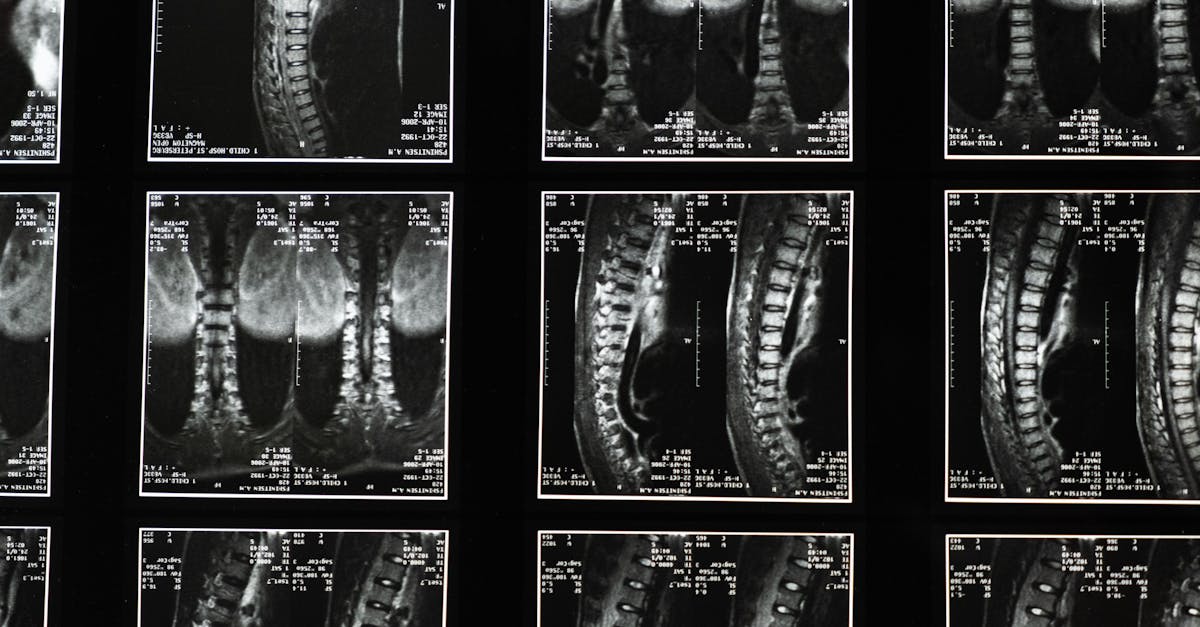

If you’re looking for effective strategies for sciatica pain relief, consider exploring 5 key ways Pulse Align might help you cope. Studies show that up to 80% of adults experience issues with lower back pain at some point in their lives, often stemming from conditions like herniated discs or spinal stenosis. Pulse Align’s holistic approach targets symptoms such as lower back pain when bending over and incorporates tailored lower back pain exercises, including core strengthening exercises and pelvic tilts. By focusing on posture correction and proper lifting techniques, Pulse Align enhances your ability to achieve lasting wellness and improve your overall quality of life.

Sciatica can be a debilitating condition, marked by lower back pain that radiates down the legs, often leading to discomfort and restricted movement. At Pulse Align, our emphasis on neuromuscular health and holistic recalibration offers innovative methods to tackle the root causes of sciatica. This guide outlines five effective strategies, encompassing core strengthening exercises, proper lifting techniques, posture improvement, ergonomic adjustments, and sleep positions for back pain, that may help enhance your well-being.

One of the most impactful ways to address sciatica is through core strengthening exercises. Engaging in targeted activities such as pelvic tilts and planks builds stability, effectively supporting the lumbar region. This approach not only helps alleviate lower back pain but also fortifies the entire trunk, reducing the risk of exacerbating conditions such as herniated discs or spinal stenosis.

TAGMED offers an advanced Spinal Decompression Therapy, a non-surgical solution designed specifically to address moderate-to-severe disc issues such as a herniated disc, bulging disc, and spinal stenosis. By gently reducing pressure on the affected discs and nerves, this specialized technique helps enhance mobility, alleviate pain, and support your body’s natural healing process. If you’ve reached a plateau with other therapies, discover how TAGMED’s evidence-based decompression approach can help you resume an active, comfortable life.

The mechanism behind TAGMED’s neurovertebral decompression involves applying a controlled, progressive traction force to the spine. This innovative method increases the space between vertebrae, effectively reducing pressure on intervertebral discs and nerve roots. As the treatment promotes better fluid circulation in the targeted area, it helps lower inflammation and relieve pain, offering a reliable, non-invasive solution for individuals with chronic back pain and associated conditions.

The specific benefits of this non-invasive approach are significant. Patients often experience effective alleviation of chronic pain and symptoms linked to conditions like herniated discs and spinal stenosis. By reducing pressure on nerve structures and optimizing fluid circulation around the discs, TAGMED’s therapy can speed up recovery and enhance the quality of life for a wide variety of patients seeking relief from persistent discomfort.